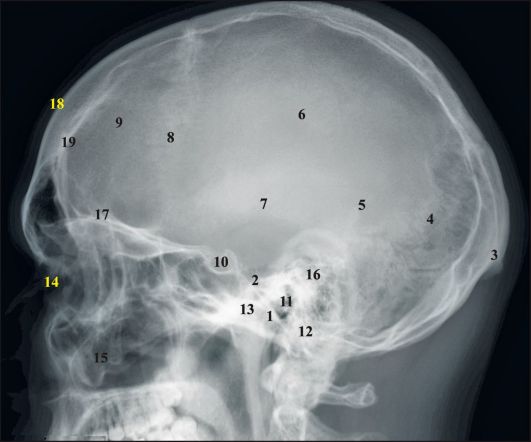

Анатомия детского черепа: Рентгеновские снимки и описание